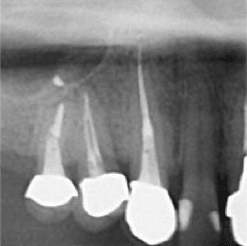

下の画像ですが、「黒い部分」が神経の入っている管であり、このすべてを綺麗に清掃する必要があります。

当院で処置した症例をご紹介します。

他院で抜歯と言われてしまった歯でも抜歯せずに対処した症例も多数あります。

黒い影が出ている部分が問題の個所で(根尖病巣)、治療後はこの影がなくなっているのが見て取れると思います。